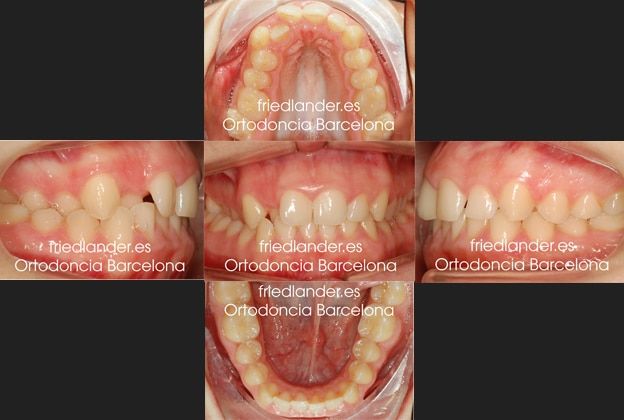

Después de unos 18 meses de tratamiento con Invisalign Full finalizamos el tratamiento y la paciente estaba muy satisfecha con los resultados estéticos y funcionales de su boca.

Al terminar el tratamiento de ortodoncia se le realizó pequeñas reconstrucciones estéticas para igualar los bordes incisales y dar mejor funcionalidad a la boca.